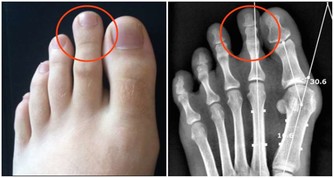

曾在門診見一久咳不癒的年輕姑娘,臉色萎黃,身材瘦弱。依照我的經驗,她肯定是當代社會“ 時髦瘦身理論 ”的受害者。詢問之下,果然如此,平時這姑娘幾乎不吃主食。

最後,她的檢查結果出來了,是肺結核。拿著報告單,可憐的姑娘欲哭無淚,一個靠打工賺取微薄收入的小女子,拿什麼來承擔後面昂貴的醫藥費?

主食不足,很可能是肺結核的重要原因之一。